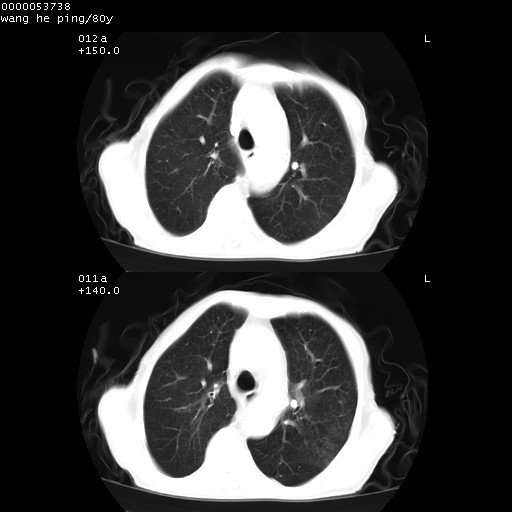

以下是引用黑白光影在2008-8-28 22:33:00的发言:[br]右肺中央型肺癌伴阻塞性肺炎,肺癌肺转移。

以下是引用lshx在2008-8-28 22:06:00的发言:[br]1.右肺中心型肺癌伴阻塞性肺炎,不除外双 肺早期转移。[br]2.心包积液。

以下是引用随光逐影在2008-8-29 7:40:00的发言:[br]1)右肺中心型肺癌伴阻塞性肺炎,肺内转移。2)心包积液(少量)。

以下是引用wqs571018在2008-8-28 21:56:00的发言:[br]右肺中心型肺癌伴阻塞性肺炎可能。

以下是引用liuyue在2008-8-28 22:46:00的发言:[br]1.右肺中心型肺癌伴阻塞性肺炎。[br]2.心包积液(少量)。